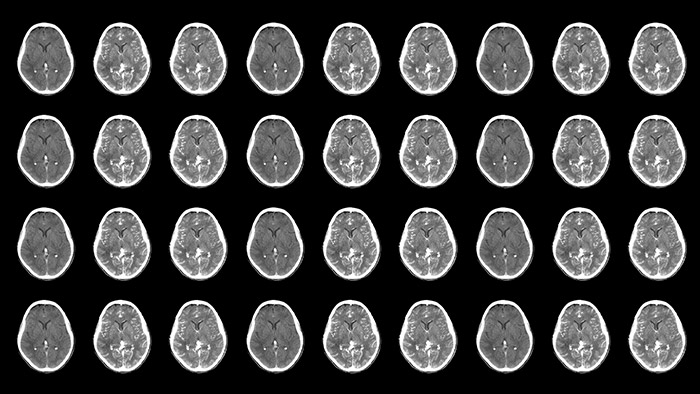

Improved neuro CT-like cone beam CT images (CBCT) to identify ischemic changes in the Angio suite. The advanced protocol with dual-axis acquisition trajectory and improved reconstruction software results in improved image appearance, compared to conventional CBCT acquisition techniques.

Offers acquisition of two consecutive contrast-enhanced CBCT scans of the brain. In the case of a stroke patient with a suspected large vessel occlusion, this allows the identification of the vessel occlusion in the first phase and the presence of collateral vessels in the second phase.